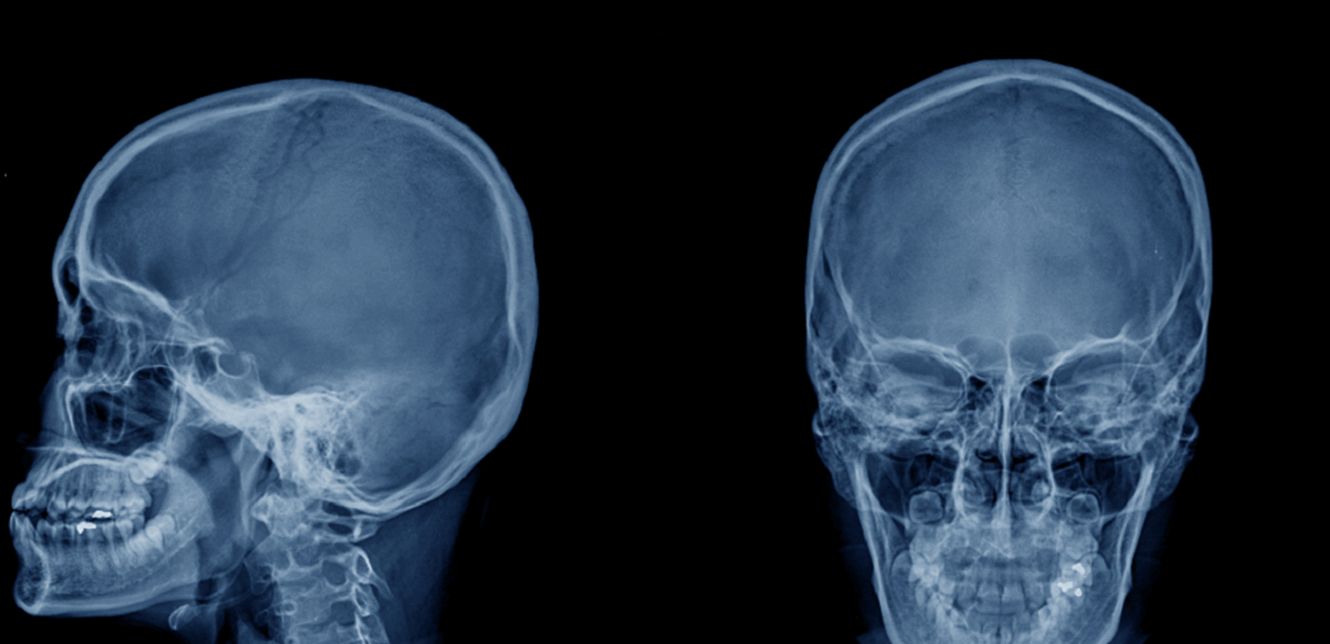

تتمتع خلايا نخاع العظام في الجمجمة باستجابة مميزة للمرض، ويقول العلماء إن هذا يعني أن الجمجمة يمكن أن تكون وسيلة مفيدة لمراقبة الالتهاب في الدماغ وربما لعلاجه.

يقترح فريق بحثي من ألمانيا والمملكة المتحدة، يبحث في رد الفعل هذا، أن النتائج التي توصلوا إليها يمكن أن تكون بمثابة تقنية غير جراحية لتصوير الجمجمة.

وفي تجارب لتصوير عينات الدماغ البشري والسحايا والجمجمة، استخدم الفريق تنقية الأنسجة مع التصوير الثلاثي الأبعاد.

وسمحت العملية للضوء بالمرور من أجل الفحص المجهري لأنسجة المخ والجمجمة.

ولاحظ الباحثون البنية الخلوية لوصلات الجمجمة والسحايا (SMCs) التي تمتد أقرب إلى سطح الدماغ مما كان يُعتقد سابقا، وغالبا ما تخترق ذلك الغشاء السحائي الخارجي والأكثر صلابة، "الأم الجافية".

ويعتقد العلماء أن اكتشافاتهم الجديدة حول الاستجابة المناعية للجمجمة تشير إلى أنه من الممكن اكتشاف التهاب الدماغ بأكثر من مجرد مسح لجمجمة المريض.